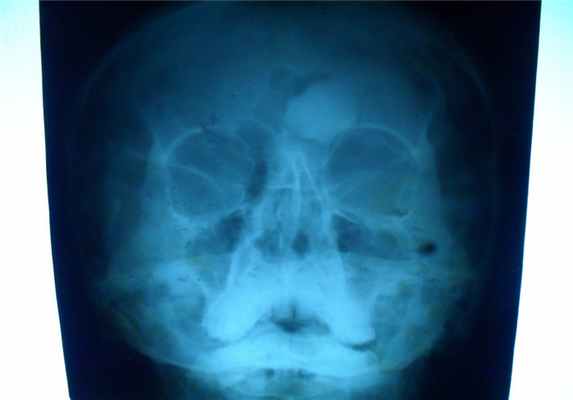

Это сосудистая опухоль, исходит из костного мозга тех костей, которые содержат красный костный мозг, может наблюдаться в любом возрасте и не зависит от пола, излюбленная локализация тела позвонков и плоские кости черепа, протекают бессимптомно.

При локализации гемангиомы в плоских костях свода черепа происходит:

- вздутие кости и разрушение коркового слоя, надкостница приподнимается опухолью,

- характерен структурный рисунок – из центра опухоли к ее поверхности лучеобразно или веерообразно рассыпаются тонкие и более грубые костные балки.